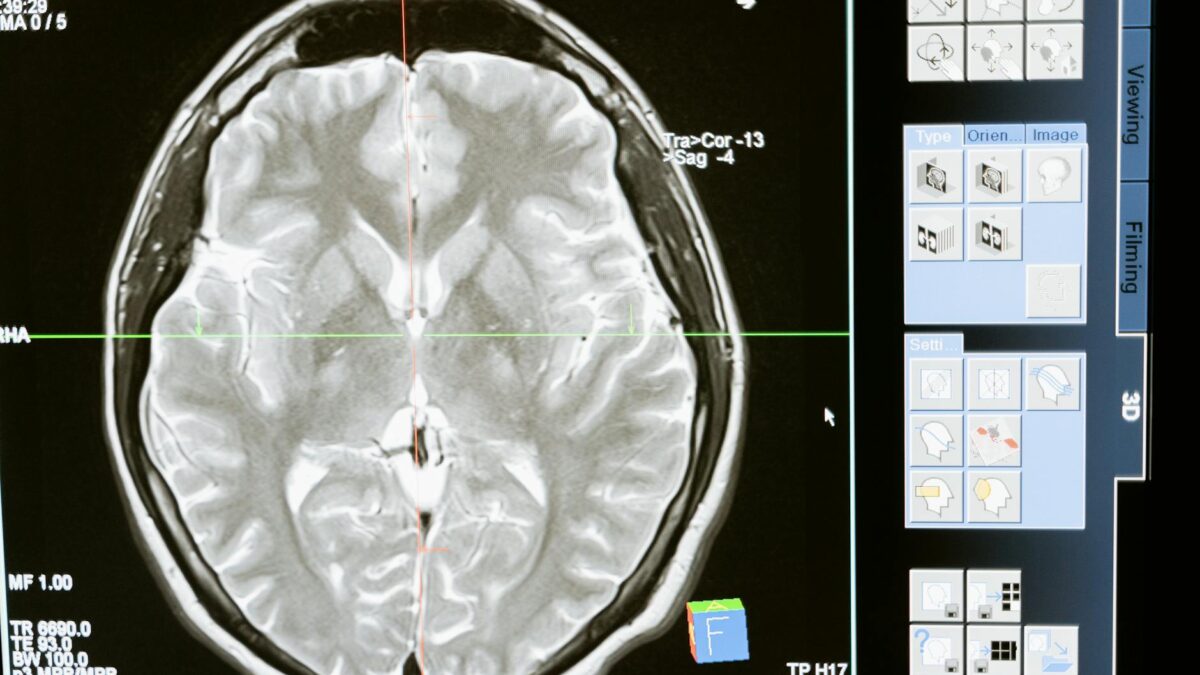

The landscape of brain-computer interfaces (BCIs) is on the brink of a significant transformation, with Science Corporation, a pioneering venture founded by former Neuralink president Max Hodak, gearing up to implant its first brain sensor in a human subject. This bold step underscores a growing trend in the BCI field that seeks to merge biological adaptability with technological advancement, potentially setting a new standard for neurological treatments and enhancements.

The brain sensor in question is a pea-sized device embedded with 520 electrodes designed to interface directly with the brain’s surface. Unlike traditional electrodes that can lead to limitations in performance and adaptability, this new sensor is aimed at creating a more seamless integration with brain tissue. The hope is that by utilizing biological materials and innovative designs, Science Corp can achieve a level of precision and functionality that outpaces existing technologies.

The upcoming trials, anticipated to commence in 2027, mark a pivotal point in the evolution of BCIs. As Science Corp prepares for the initial human implantation, the implications of successful trials could revolutionize how we approach neurological disorders, brain injuries, and cognitive enhancements. The integration of a biological sensor offers a promising alternative to existing electronic solutions that often suffer from limited adaptability and risk of rejection by the body.

The applications for such a technology are vast. From assisting individuals with neurological disorders like epilepsy or Parkinson’s disease to enhancing cognitive functions in healthy individuals, the implications are profound. Furthermore, as our understanding of the brain deepens, the potential for BCIs to facilitate communication for those with disabilities or paralysis becomes increasingly viable.